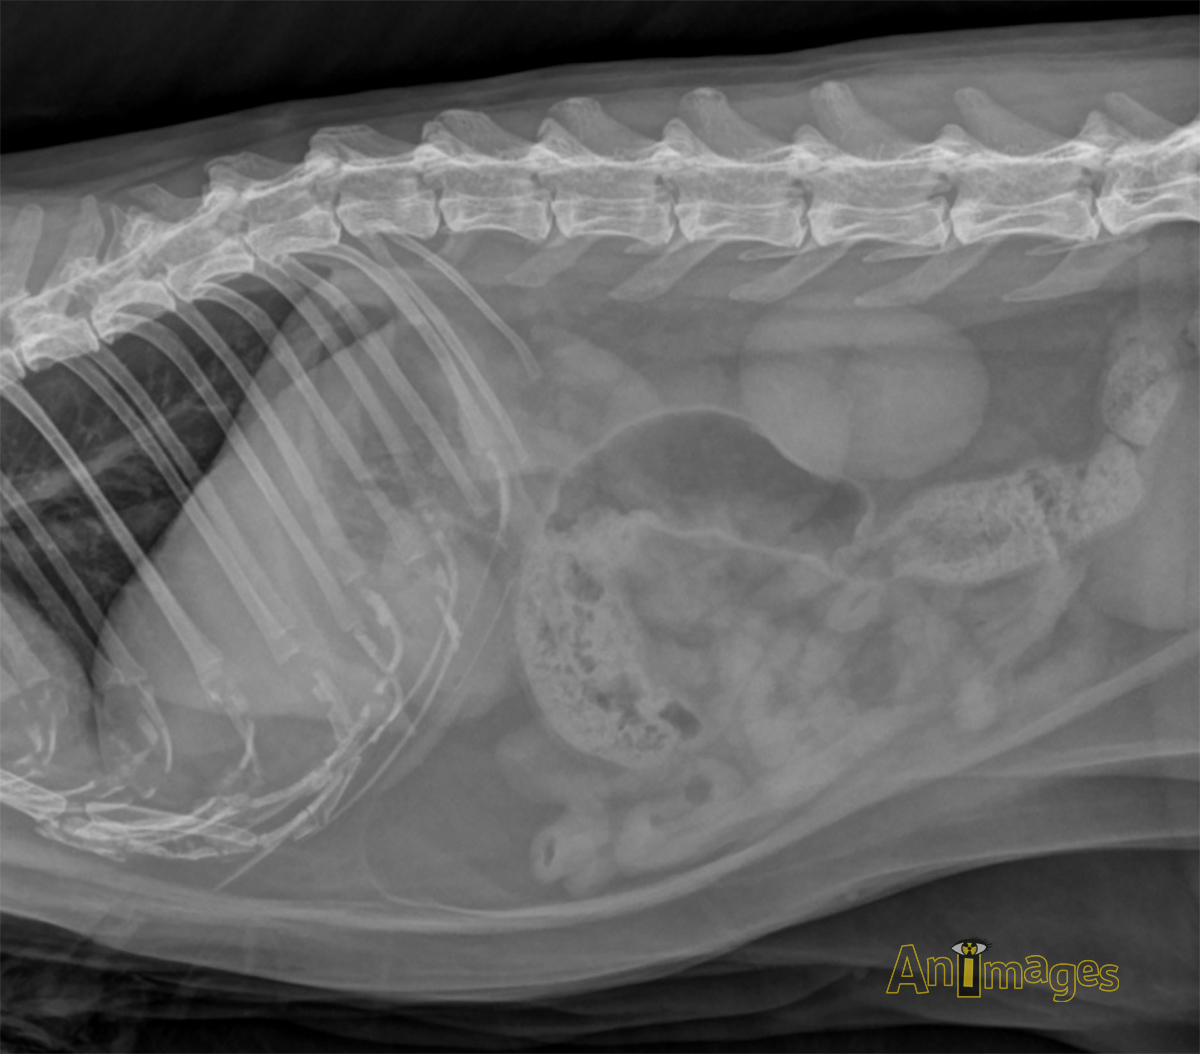

latérale droite